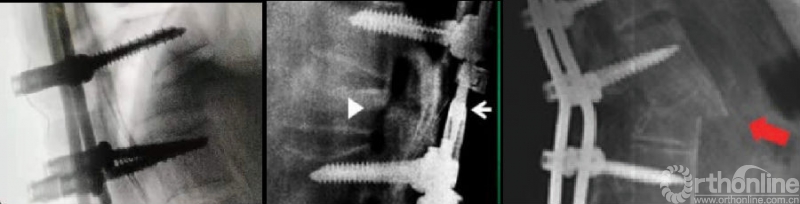

Chang最早报道矢状面移位,定义为截骨平面头侧椎体后下缘与尾侧椎体后上缘之间位移超过2mm[1]。成俊遥:<4mm的ST较难避免且通常无明显诱发因素,可视作截骨操作误差范围[2]。ST判定标准的不同导致其发生率的报道存在着较大的差异(1.6%-27%)。

ST常伴随着椎板对硬膜和神经根的挤压,迅速而有效的椎板减压对于挽救神经功能至关重要。椎弓根对于硬膜和神经根的压迫同样不容忽视,Chang等报道的5例存在神经症状ST患者中,4例源于椎弓根对神经根的挤压,建议必要时需行椎弓根切除术。

ST的复位对于神经的减压更直接有效,并可以避免椎板和神经根切除减压过程中硬膜损伤风险。复位主要通过调整截骨平面上下椎体置钉深度以及调整矫形棒铰链点水平进行。

尽管在调整置钉深度过程中取下一侧矫形棒存在进一步加重矢状位脱位的风险,笔者认为已经发生的ST上下截骨面多数处于嵌插位置,暂时处于稳定状态,此时在保留对侧矫形棒固定的状态下,交替进行椎体置钉深度和矫形棒铰链点水平的调整是相对安全的。